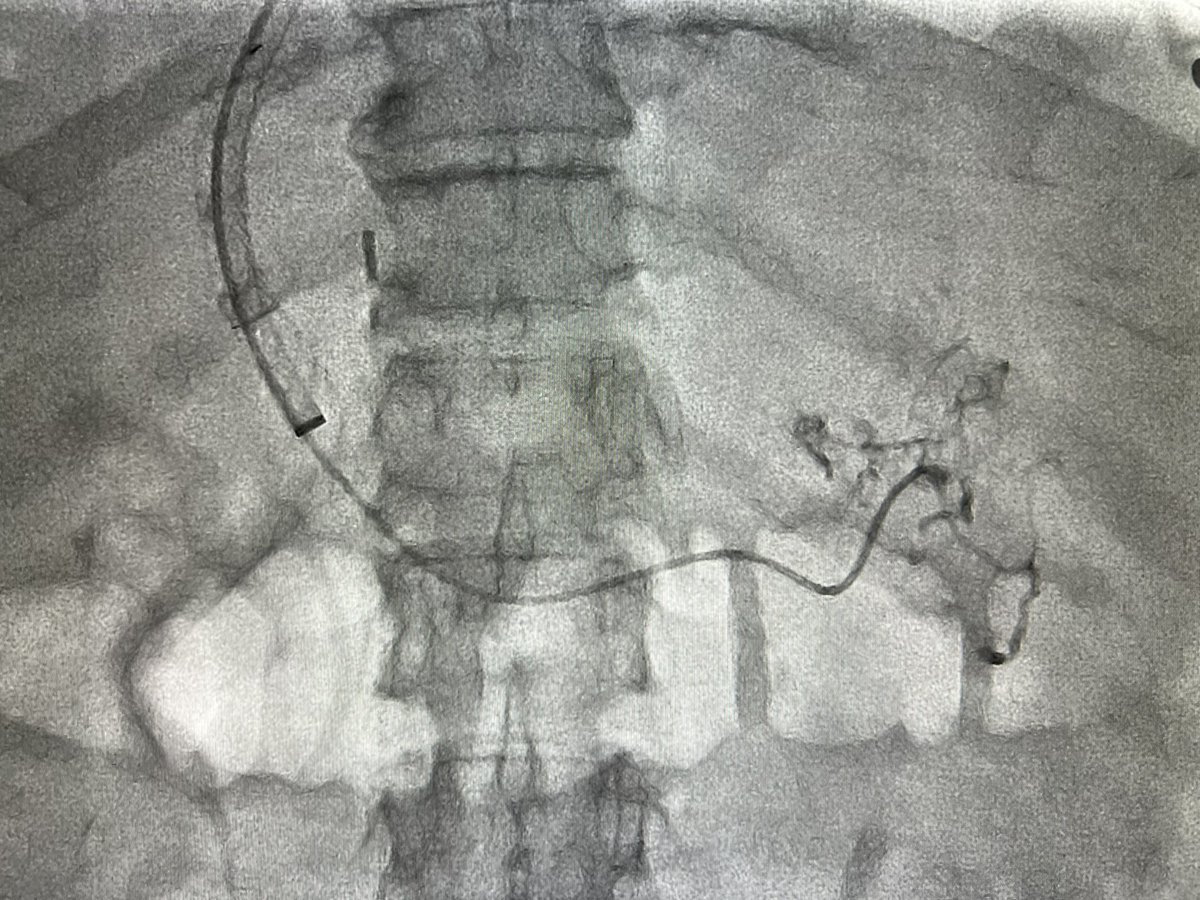

في إنجاز طبي يعد الأول من نوعه في المنطقة الشرقية، تم بنجاح إجراء منظار للقنوات الصفراوية في الكبد عن طريق الجلد، مع تنظيف القنوات الصفراوية وأخذ عينة، وذلك في وحدة الأشعة التداخلية بمستشفى الملك فهد الجامعي.

أتوجه بجزيل الشكر والتقدير إلى إدارة قسم الأشعة التشخيصية وإدارة مستشفى الملك فهد الجامعي وإدارة جامعة الإمام عبد الرحمن بن فيصل على دعمهم المستمر وتوفير الإمكانيات اللازمة لإنجاز مثل هذه الإجراءات المتقدمة، مما يعزز من جودة الرعاية الصحية المقدمة للمرضى.

افتتح عميد كلية الطب د.بندر الجفن والمدير التنفيذي للشؤون الصحية في #المدينة_الطبية بـ #جامعة_الملك_سعود د. عبدالعزيز الثنيان ورئيس قسم الاشعة والتصوير الطبي د.نوران ملا ورشة عمل علاج أمراض القنوات الصفراوية باستخدام تقنية المناظير عن طريق الجلد بمشاركة نخبة من الأطباء المتخصصين في مجال الأشعة التداخلية، تم من خلالها طرح أبرز المستجدات والاكتشافات والتجارب في علم الأشعة التداخلية والمناظير، حيث تعتبر هذه الورشة هي الأولى من نوعها على مستوى العالم.

وكانت ورشة العمل تدار بالاستعانة بخبرات نخبة من الاستشاريين تضم د. أحمد الأحيدب @alehaideb ، د. بسام الرحيلي @DRSTINGRAY ، د. تركي الفرحان @Turki_fs ، د. سلطان الحربي ، د. عبدالله الجهني @AljohaniMD ، د. علي الجمعة @AljomahAli1 ، د. عمار العتيبي @DrAmmarAlotaibi ، د.يحيى العسيري @YAALSAAS